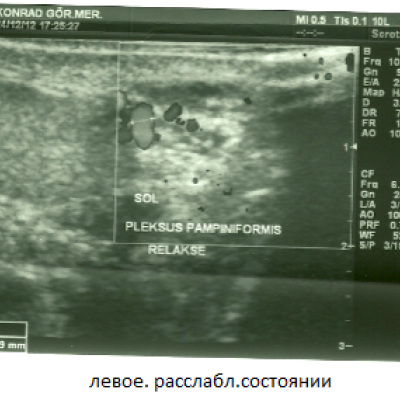

Мужу сделали УЗИ. Доктор сказал, что у мужа двустороннее варикоцеле. Нужна операция. Вот результаты УЗИ:

Заметно расширены вены левого гроздевидного сплетения и извилистость. Максимальный диаметр вен в расслабленном состоянии 2.09 мм., при проведении пробы Вальсальве 3,50 мм. В положении лежа при проведении пробы Вальсальве количественное увеличение венозных структур, увеличение диаметра до патологического размера. В режиме ЦДК, при проведении пробы Вальсальве был выявлен кровоток в обратном направлении - рефлюкс .

Фото тоже я прикрепила